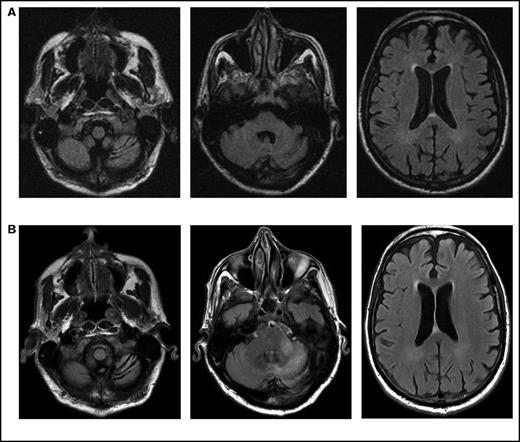

Serial imaging of a patient diagnosed with CLL. Cancer-directed therapy included >6 months of rituximab and idelalisib. (A) Initial magnetic resonance imaging performed 2 months after the onset of headaches and balance disturbance (gait instability and repeated falls) depicting the asymmetric atrophy of the left cerebellum, which was not present in imaging performed 7 months earlier (not depicted). Fluid-attenuated inversion recovery (FLAIR) signal abnormalities are not present elsewhere. (B) Imaging repeated 3 months later (1 month prior to death) showing the continued atrophy of the left cerebellum with new confluent areas of FLAIR signal throughout the left cerebellum and left cerebellar peduncle without enhancement. Again, no FLAIR signal abnormalities are seen in the cerebrum.